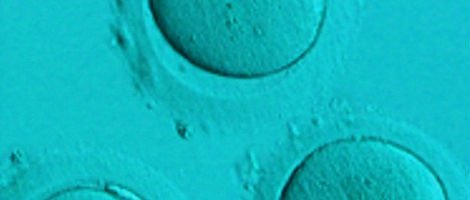

Uma dessas alternativas é a doação de ovócitos. Uma mulher jovem doa os seus ovócitos a uma outra mulher e esses ovócitos são fertilizados com o esperma do parceiro da mulher receptora. Posteriormente, os embriões são transferidos para o útero da mulher receptora. É uma técnica simples e eficaz com boas taxas de sucesso.